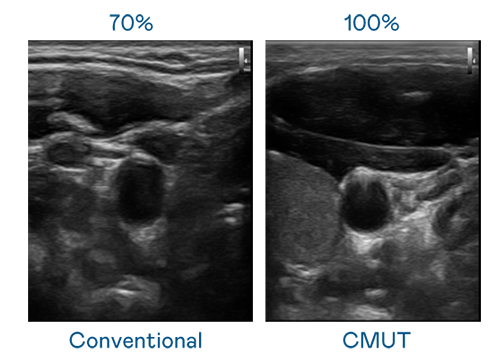

CMUT 技术是一种用电容式微机电元件来产生超音波讯号的技术。与传统 PZT 压电式技术相比,CMUT 频宽增加 30%,更宽频的超音波讯号让影像解析度大幅提升,是实现高影像品质医疗超音波扫描、促进精准医疗发展的关键技术。

超音波影像的解析度高低,首先取决于探头能发出的讯号频宽。德晋贵宾厅 CMUT 可提供高清晰的超音波讯号,提供高频宽、高灵敏度、影像纹理细节更高的超音波影像,协助医护人员缩短影像判读时间及利用精准的医疗影像进行诊断。